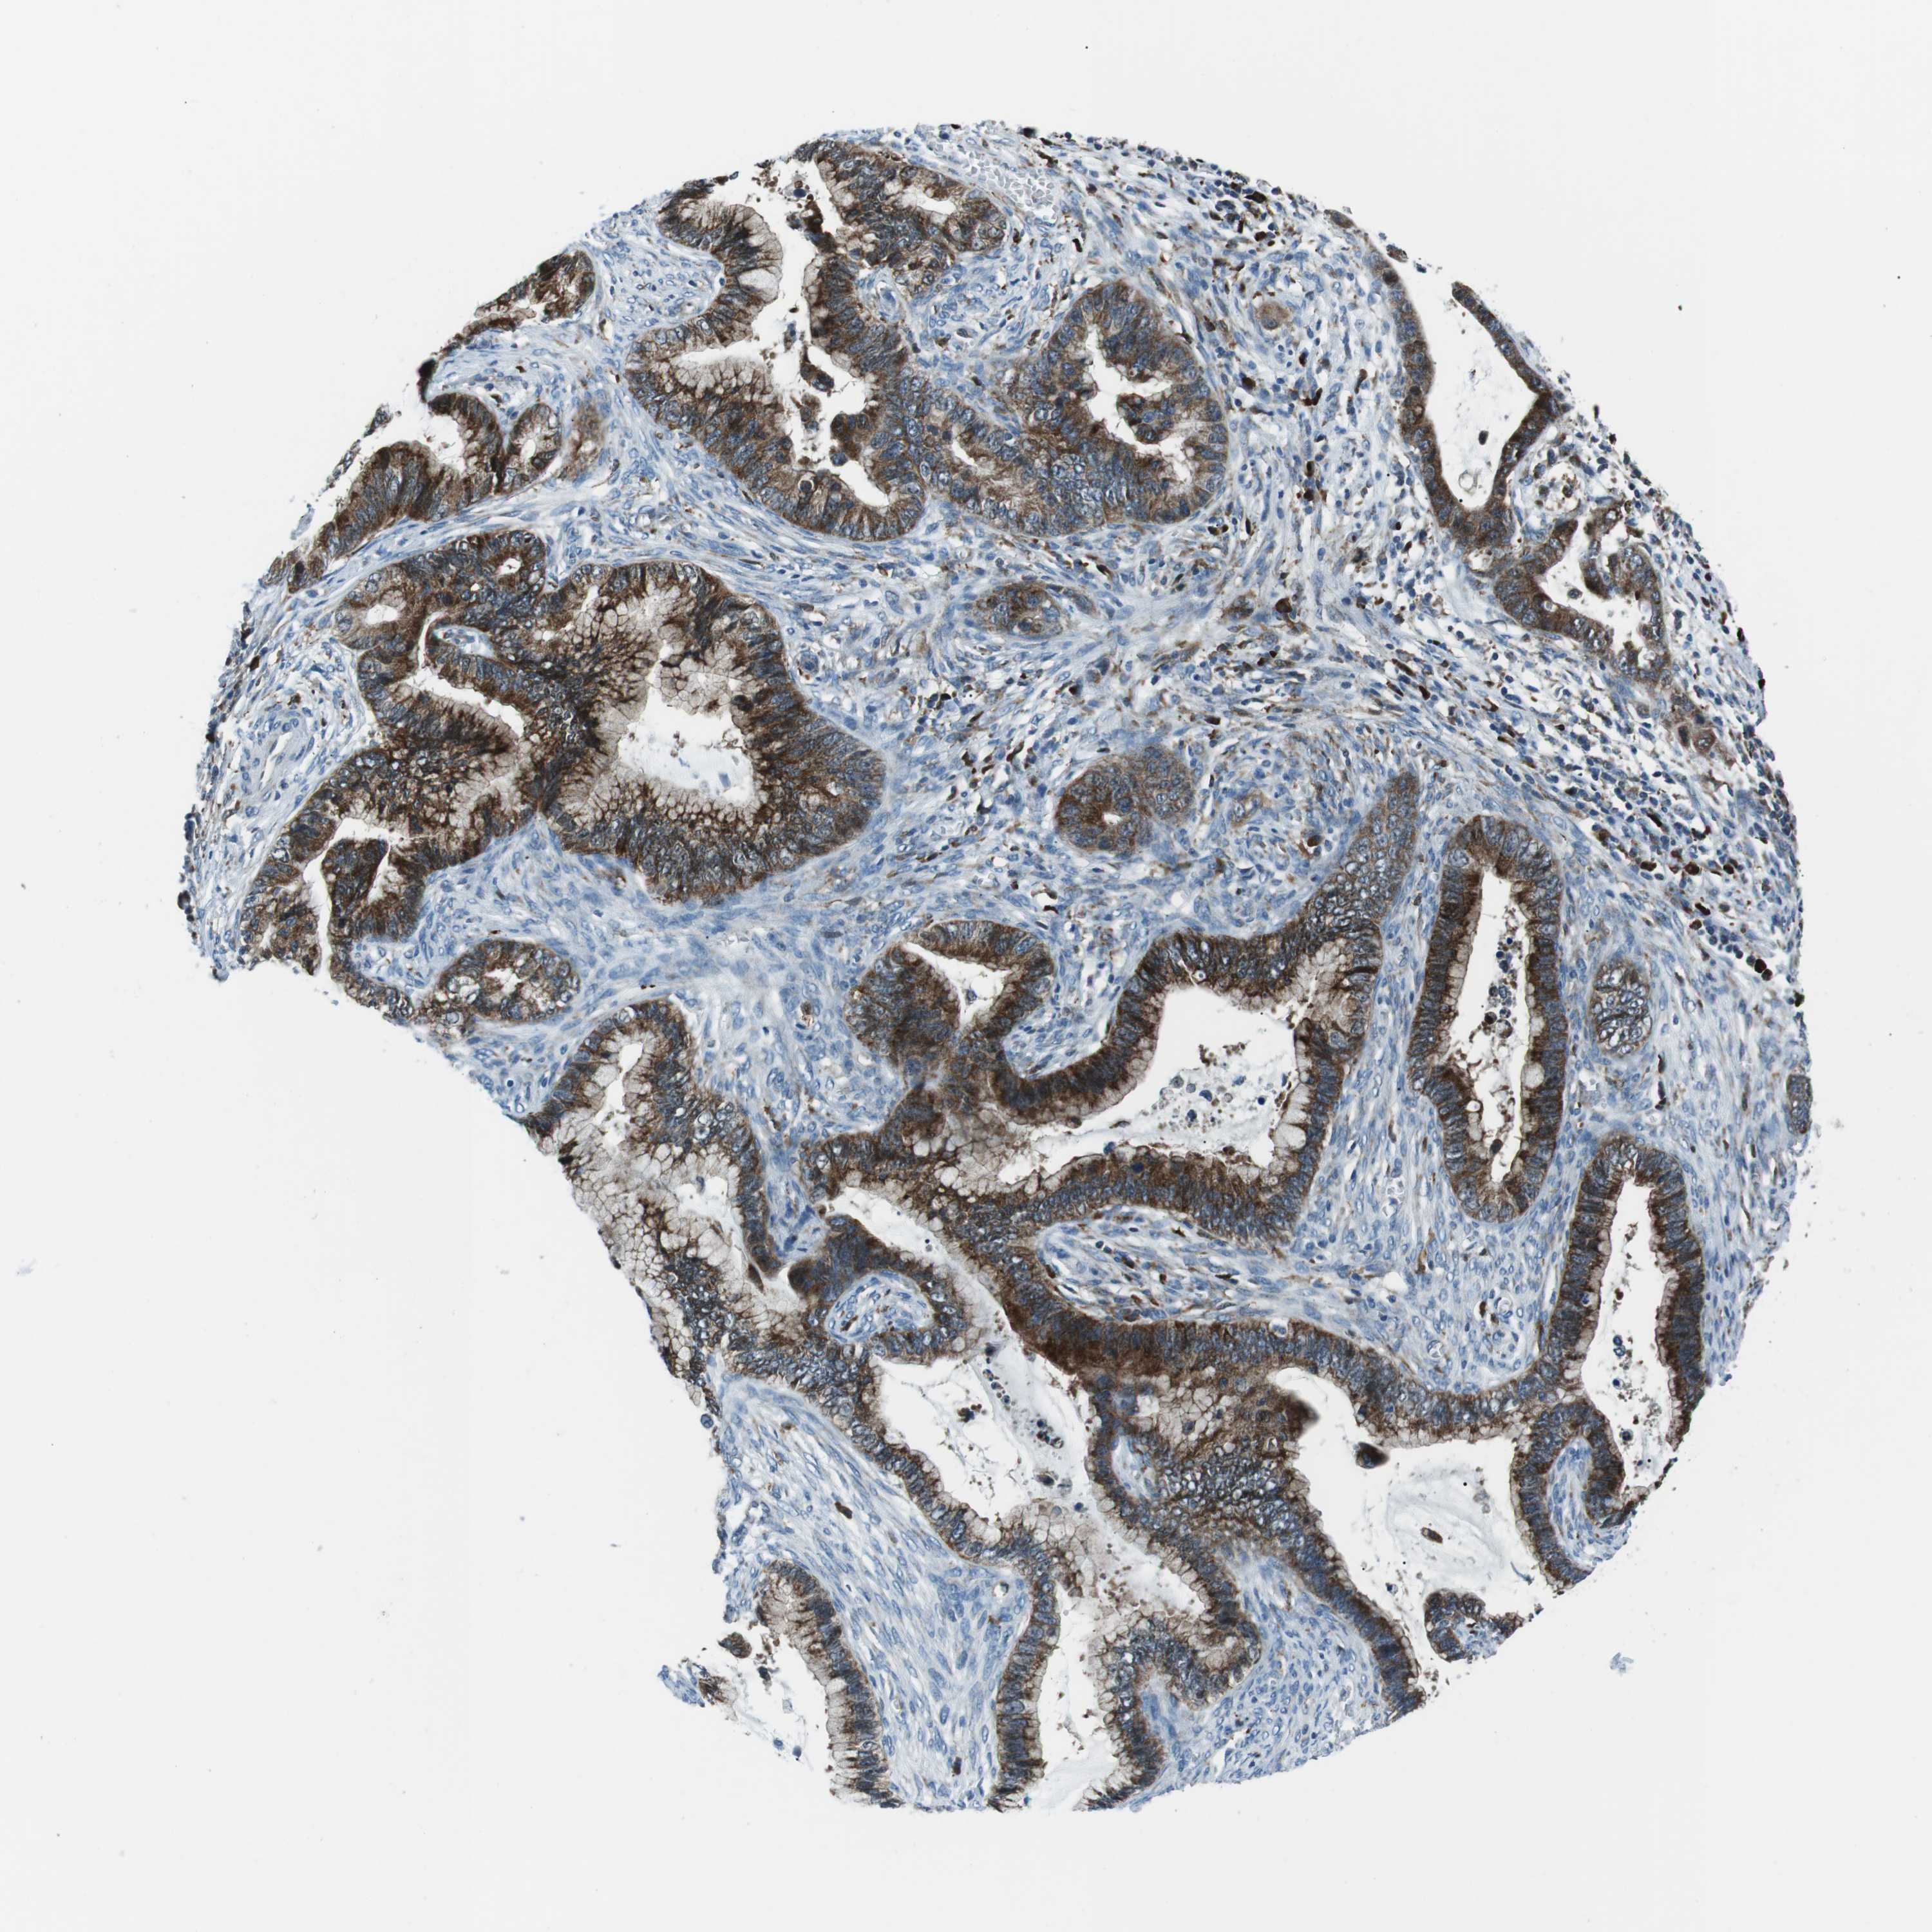

CERVICAL CANCER - Protein expressioni

A mouse-over function shows sample information and annotation data. Click on an image to view it in a full screen mode. Samples can be filtered based on level of antibody staining by selecting one or several of the following categories: high, medium, low and not detected. The assay and annotation is described here.

Note that samples used for immunohistochemistry by the Human Protein Atlas do not correspond to samples in the TCGA dataset.

Antibody stainingi

Antibody staining in the annotated cell types in the current human tissue is reported as not detected, low, medium, or high, based on conventional immunohistochemistry profiling in selected tissues. This score is based on the combination of the staining intensity and fraction of stained cells.

Each image is clickable and will lead to virtual microscopy that enables deeper exploration of all samples and also displays staining intensity scores, fraction scores and subcellular localization as well as patient and tissue information for each sample.

Antibody HPA038309

Antibody HPA038310

Antibody CAB009333

Antibody CAB016291

Squamous cell carcinoma, NOS